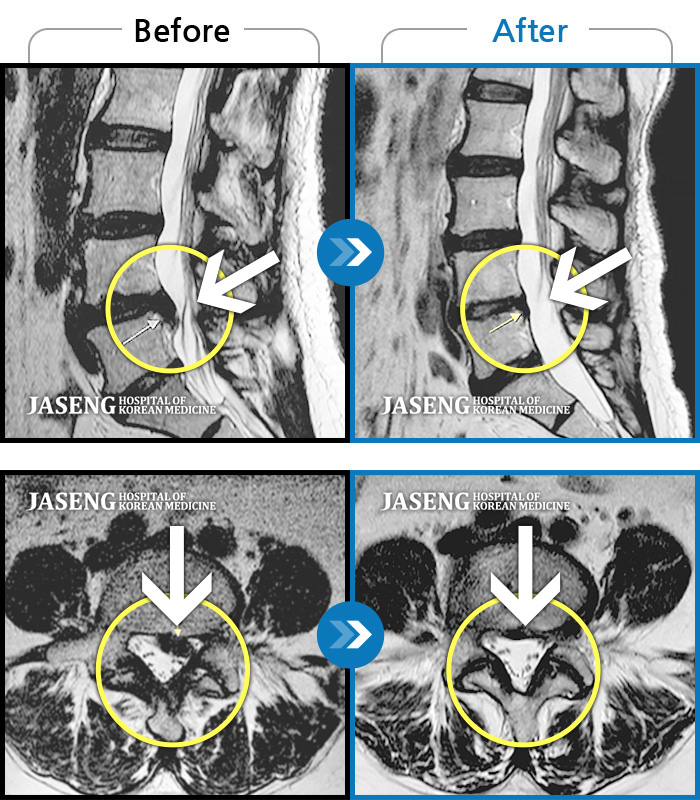

Before

After

허리와 양쪽 엉덩이 통증 및 좌측 둔부, 대퇴, 소퇴 후면부 통증 및 저림

2013.05.14 ~ 2014.04.23